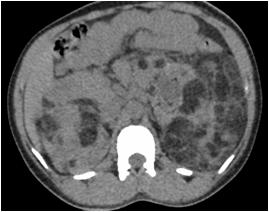

Radiological imaging was done in all the cases. USG findings revealed solitary masses in 45 cases (80.35%) and diffuse masses in 11 (19.64%). Solitary masses were around 45 in number out of which 30 were diagnosed as HCC. Right lobe had around 30 (66.7%) whereas left lobe had 15 (33.33%) masses respectively. Maximum (SOL’s) observed showed hyper-echogenicity present in 43 cases (76.78%). Heterogenous echotexture was observed in 6 cases (10.71%) (Fig 1).

CT scan was done in two patients which showed multiple well defined hyperdense lesions and hypodense lesions in another patient. Cyto-radiological correlation of hepatic masses was seen in 94% cases (Fig 2).

Fig 1 — USG liver showing well defined heteroechoic lesion in left lobe

Fig 2 — CT liver showing multiple enhancing focal hepatic lesions suggestive of metastasis